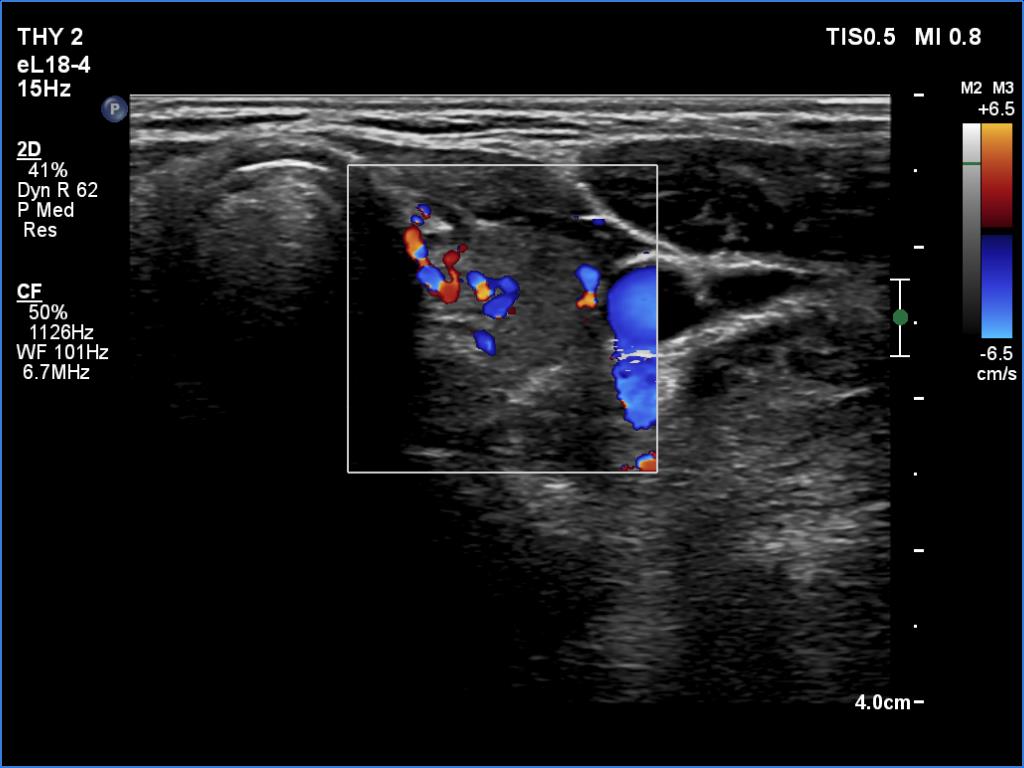

Right lobe, longitudinal scan

Left lobe, transverse scan, color Doppler mode. The vascularity became average.